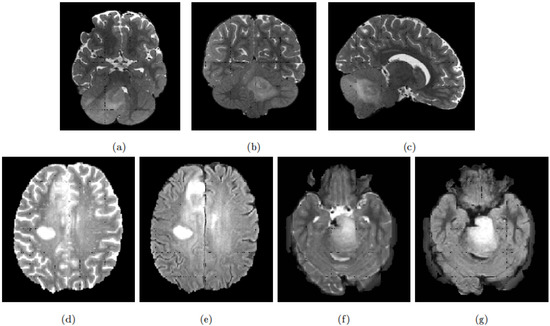

We chose You Only Look Once (YOLO) [34,35] as our object-detection framework. For the segmentation, we benchmarked UNet [36] and Bounding-Box UNet (BB-UNet) [28]. It must be noted that both UNet and BB-UNet receive the whole 2D images as input for the training and inference; additionally, BB-UNet receives also an a priori bounding-box used internally to (non-exclusively) focus the learning segmentation process. Consequently, we examined two different procedures to combine the object-detection and segmentation. We called our first procedure Parallel YOLO UNet (pYU). In pYU, both YOLO and UNet are trained independently. In the inference phase, YOLO-generated bounding-boxes are merely used to mask UNet predictions, thus eliminating all segmented voxels outside the bounding-box. In our second approach, called Sequential YOLO BB-UNet (sYBBU), YOLO and BB-UNet are trained independently, but during inference, YOLO-generated bounding-boxes are provided as additional input to BB-UNet. As with pYU, we also used the bounding-boxes to mask the segmentation output.

Figure 2 illustrates the two approaches, pYU and sYBBU, sketched in their inference stage. Supplementary Figure S1 and Figure S2 show the different training and inference possibilities and combinations.

Figure 2. The two approaches pYU and sYBBU. (a) Parallel YOLO UNet (pYU) model; (b) Sequential YOLO BB-UNet (sYBBU) model.